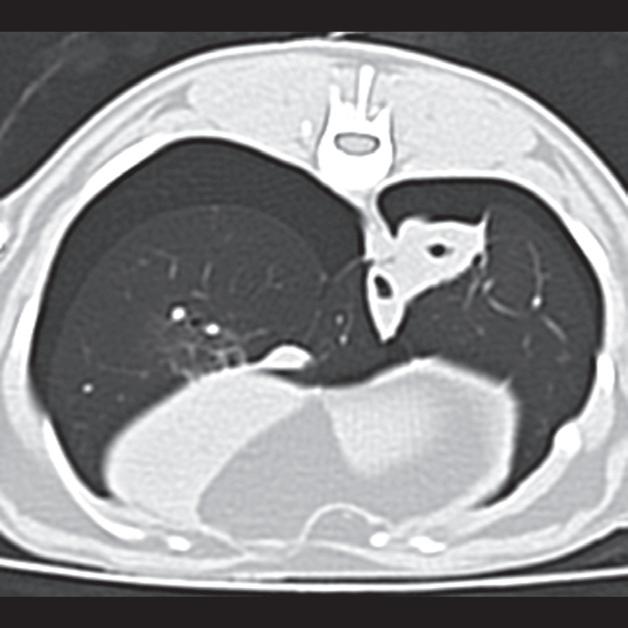

Rycina 4.6.4. Kardiogenny obrzęk płucny (kot) TK

Badanie wykonano u 4-letniej, kastrowanej samicy kota domowego krótkowłosego dializowanej z powodu niewydolności nerek. U pacjentki obserwowano echokardiograficzne objawy łagodnej kardiomiopatii. W momencie wykonywania tomografii komputerowej kot był umiarkowanie przeciążony płynami. Obraz na ryc. a jest reprezentatywnym obrazem na poziomie tylnej części klatki piersiowej, a obrazy przedstawione na ryc. b i c stanowią powiększenie ryc. a. Niewielka objętość płynu opłucnowego unosi powietrzne płuco (a – czarna strzałka). Widoczny jest łagodny, rozproszony wzrost atenuacji płuc z dodatkowymi, licznymi zmianami w typie matowej szyby. Wydaje się, że te ostatnie nacieki są najbardziej widoczne wokół naczyń płucnych (a–c – białe strzałki). Badanie pośmiertne potwierdziło, że nacieki były spowodowane obrzękiem płuc. W tym przypadku obrzęk prawdopodobnie był wynikiem względnej niewydolności komór serca spowodowanej kardiomiopatią i przeciążeniem płynami